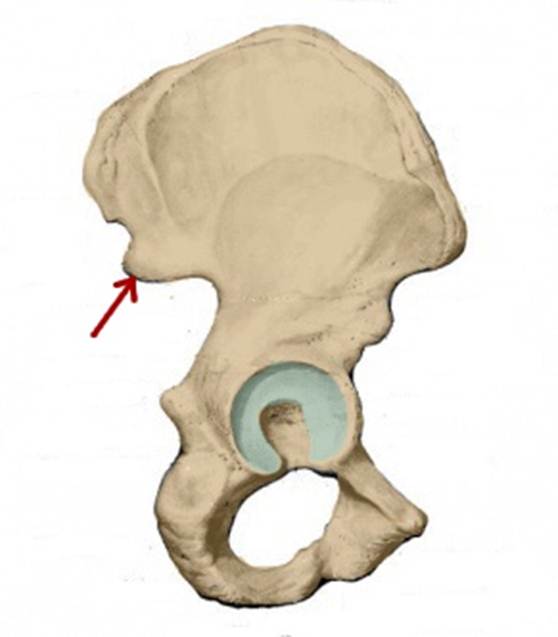

I:

S: Стрелка указывает на os pubis (латинский язык).

I:

S: Стрелка указывает на os ilium (латинский язык).

I:

S: Стрелка указывает на os ischii (латинский язык).

I:

S: Стрелка указывает на ramus superior ossis pubis

I:

S: Стрелка указывает на ramus inferior ossis pubis

I:

S: Стрелка указывает на ramus ossis ischii

I:

S:Стрелка указывает на spina iliaca posterior superior

I:

S:Стрелка указывает на lambium internum

I:

S: Стрелка указывает на spina iliaca posterior inferior

I:

S: Стрелка указывает на tuber ischiadicum (латинский язык).

I:

S: Стрелка указывает на foramen obturatum (латинский язык).

I:

S: Стрелка указывает на tuberculum pubicum

I:

S: Стрелка указывает на facies lunata (латинский язык).

I:

S: Стрелка указывает на spina iliaca anterior inferior

I:

S: Стрелка указывает на incisura ischiadica minor

I:

S: Стрелка указывает на incisura ischiadica major

I:

S: Стрелка указывает на incisura acetabuli

I:

S: Стрелка указывает на spina iliaca anterior superior